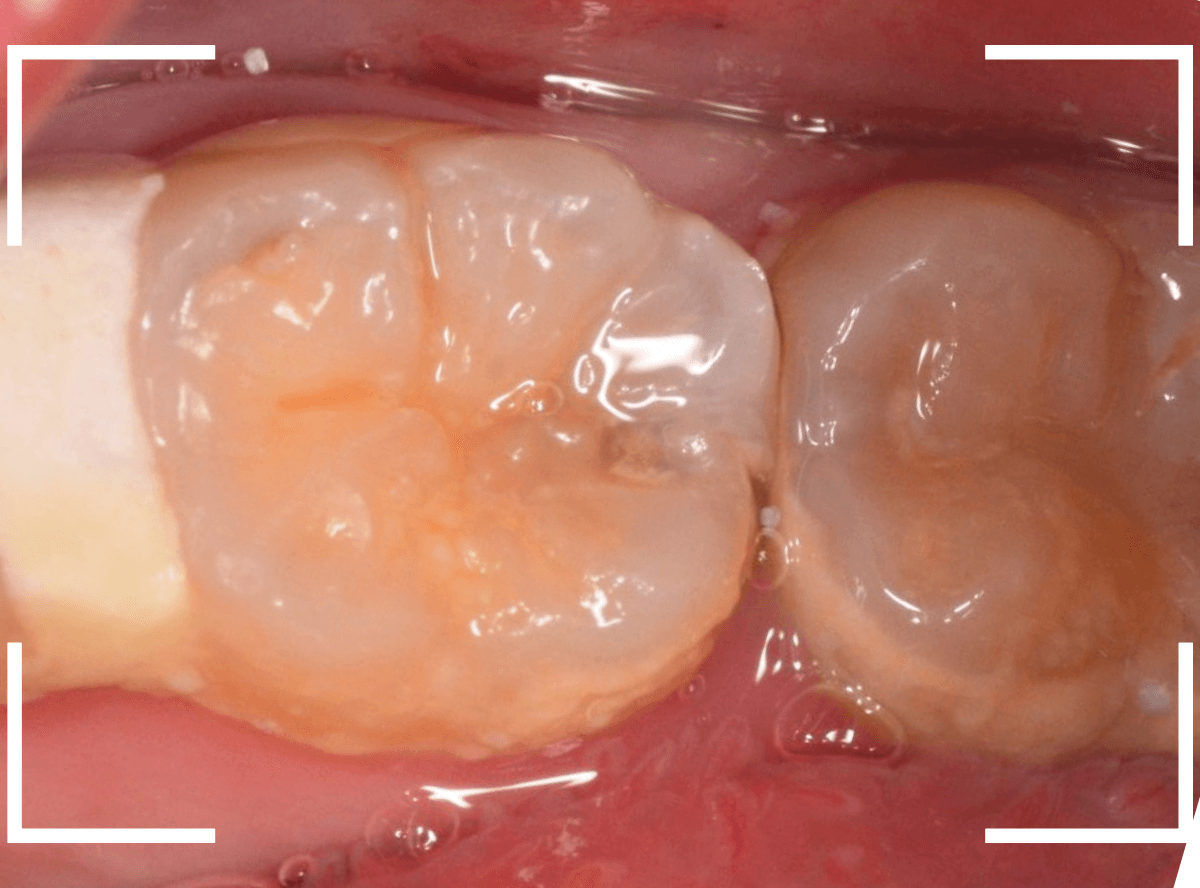

Case.24 レジンの下で虫歯が進行

上の奥歯の虫歯が見つかった患者さんです。

初診のチェックの際に、上から目視すると、レジンがつめてある〇部分が薄暗く黒くなっているので、これは虫歯があるな、とわかりました。

治療を開始します。

先ほどの黒く見えた部分は少し削るとすぐに虫歯が出てきました。

手前の歯まで虫歯を除去した時点で、う蝕検知液で確認します。

赤く染色されている部分が虫歯です。

思ったよりも深めの虫歯ですね。

レジンを除去して虫歯をすべて治療したところです。

レジンの中も全体にうっすらと虫歯になっていました。

このくらいの虫歯でも、患者さんは自覚症状はありませんでした。